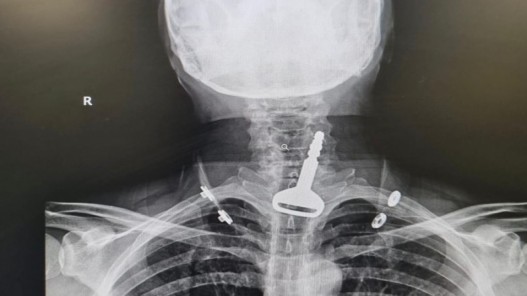

تدخل جراحي ينقذ حياة سعودي ابتلع مفتاح سيارته

عمان1:أعلنت وزراة الصحة السعودية، إنقاذ حياة مواطن سعودي ابتلع مفتاح سيارته بالخطأ، كان عالقا بالجهاز التنفسي للمريض الأربعيني، وكاد أن يودي بحياته. وذكرت الصحة السعودية، في بيان ، أن الفريق الطبي المختص بمدينة القنفذة،غرب السعودية، استغرق نحو 15 دقيقة لاستخراج المفتاح عن طريق المنظار. وأشارت إلى...